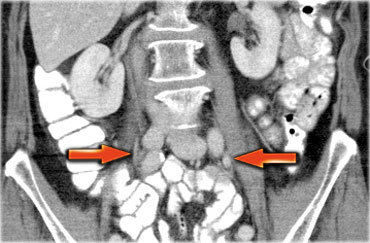

Một phương pháp hữu ích để xác định buồng trứng là theo dõi tĩnh mạch buồng trứng theo hướng đuôi.

Hãy cuộn qua các hình ảnh CT và theo dõi tĩnh mạch buồng trứng phải từ vị trí đổ vào tĩnh mạch chủ dưới, và tĩnh mạch buồng trứng trái từ vị trí đổ vào tĩnh mạch thận trái, cho đến khi xác định được buồng trứng.